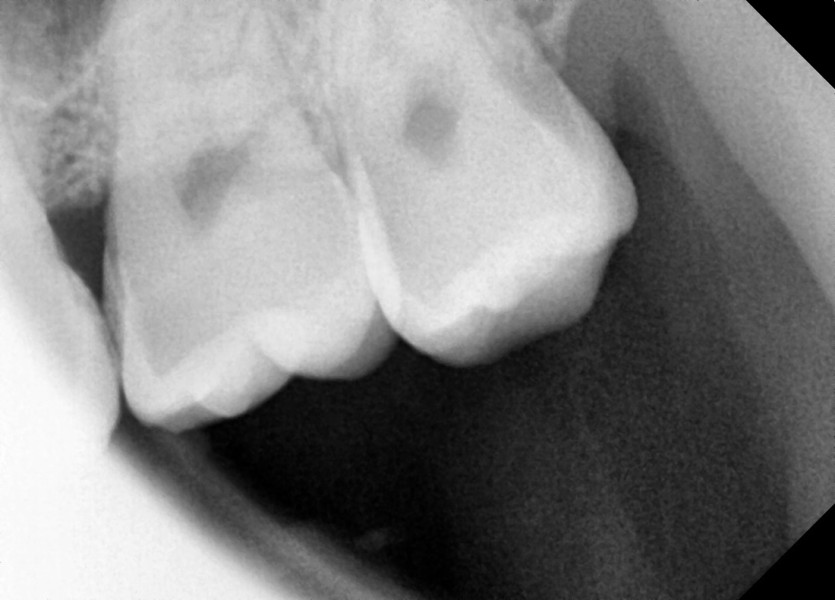

#28,38 사랑니 발치

구강 외과 전문의가 당일 발치했습니다.